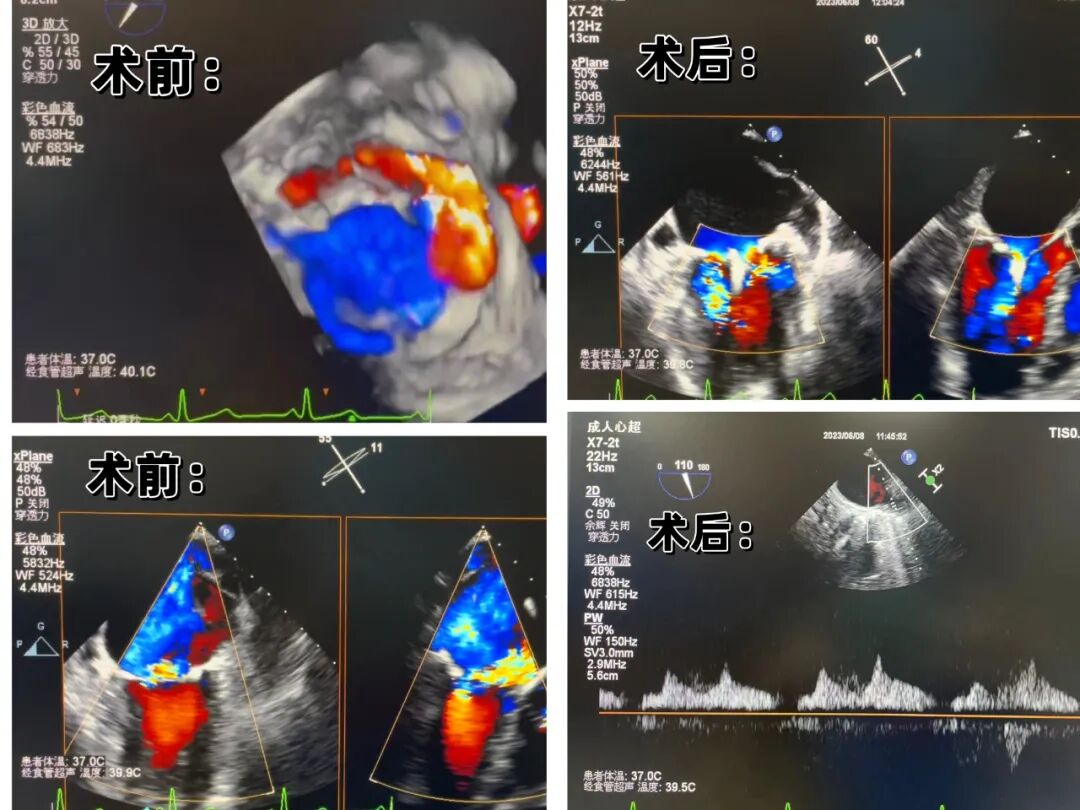

三維食道超聲顯示,患者同時存在二尖瓣脫垂導致的反流、心房嚴重擴大后導致的二尖瓣功能性反流兩種癥狀。脫垂的位置位于2區(qū)偏3區(qū)部位,后葉夾持部位瓣膜合并鈣化,后葉可夾持瓣葉較短,手術難度較大。經反復調整,楊飛主任在整個團隊的密切配合下,精準抓捕瓣膜,二尖瓣夾準確地封閉了脫垂的瓣膜,成功在2區(qū)實施了二尖瓣緣對緣鉗夾術!

術后,彩超證實患者二尖瓣反流情況得到了明顯改善:術前二尖瓣反流4+級,術后降至小于1級;肺靜脈收縮期逆流頻譜恢復正向;跨瓣平均壓差5mmHg,即刻治療效果滿意!手術順利完成后,患者當天就能夠下床活動,恢復良好。